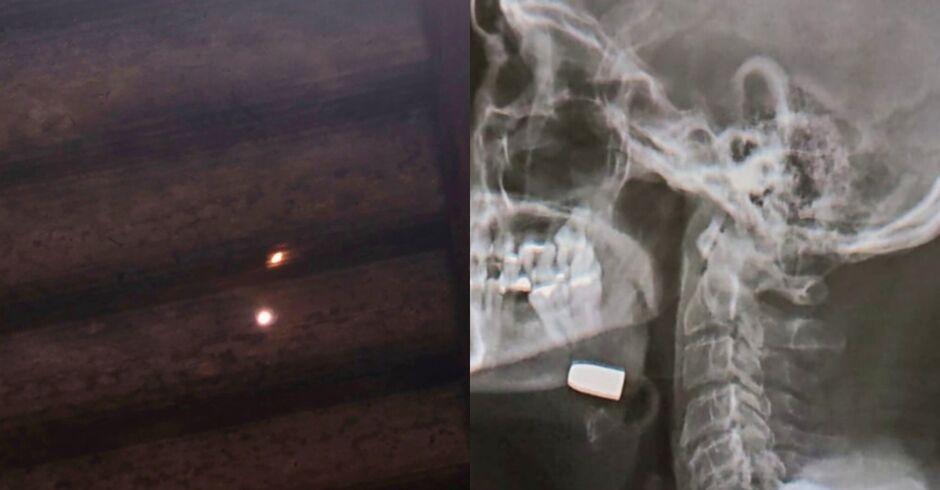

Homem de 58 anos foi atingido por uma bala perdida enquanto dormia em casa, no bairro São Bento, em Sidrolândia, a 68 quilômetros de Campo Grande O caso, registrado como lesão corporal dolosa, ocorreu na madrugada de sexta-feira (12), mas só foi confirmado na madrugada de domingo (14), após exames médicos.

Na noite de sábado (13), a vítima procurou o Hospital Beneficente Dona Elmíria Silvério Barbosa devido à piora no quadro, segundo o site Noticidade. Após a realização de exames de imagem, foi constatado que ele estava com um projétil alojado na região do rosto, sendo necessária intervenção cirúrgica para a retirada.

Ainda de acordo com a vítima, ele dormia em sua casa quando sentiu forte ardência e dor, mas não chegou a ouvir estampidos de disparo. Apenas no período da tarde de sábado (13) percebeu um buraco no teto de sua residência, possivelmente causado pelo projétil que o atingiu.